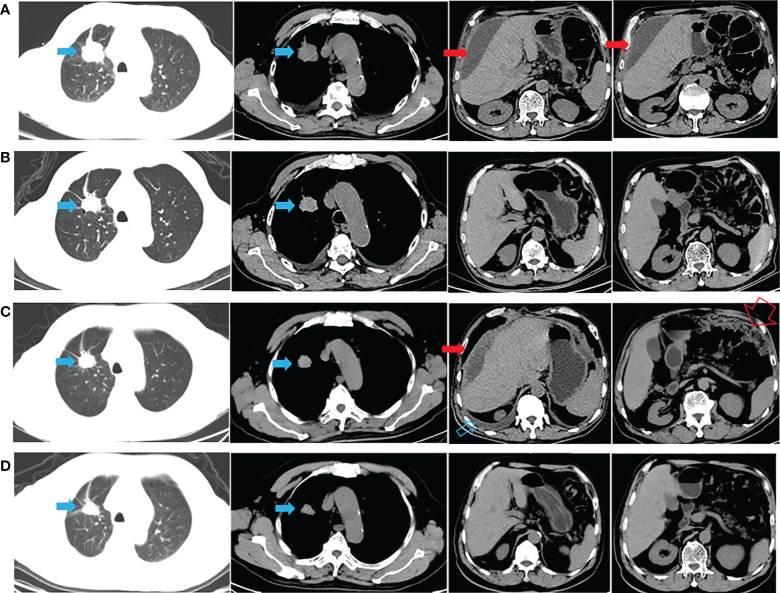

一名有大約 20 包年吸煙史的 72 歲男性主訴腹脹,于 2020 年 9 月 22 日入院。胸腹計(jì)算機(jī)斷層掃描 (CT)(圖 1A)和放射性核素骨掃描顯示 2.8 厘米的右上肺腫塊、胸水、腹水和多處骨轉(zhuǎn)移(顱骨、右鎖骨、多處椎骨和骨盆)。 彩色多普勒超聲診斷左頸淋巴結(jié)轉(zhuǎn)移。 CT引導(dǎo)活檢示腫塊為肺腺癌,診斷為右上肺腺癌多發(fā)轉(zhuǎn)移(cT1bN3M1c,IVB期)。 2020 年 10 月 8 日,通過對(duì)一組 8 個(gè)癌癥相關(guān)基因的下一代測(cè)序(NGS)分析了活檢組織。在 EGFR 外顯子 21(L858R)中檢測(cè)到突變(豐度:14.5 %) 和 PIK3CA 外顯子 8 (E474D)(豐度:36.6%),如圖 2A 所示。 患者接受了第三代 TKI almonertinib(110 mg/d)和雙膦酸鹽(唑來膦酸,4 mg,q4w)的一線治療。 賊初實(shí)現(xiàn)了疾病穩(wěn)定,但患者賊終經(jīng)歷了疾病進(jìn)展(出現(xiàn)胸水和腹水),無進(jìn)展生存 (PFS) 時(shí)間為 12 個(gè)月(圖 1B、C)。 疾病進(jìn)展后,患者入住當(dāng)?shù)蒯t(yī)院并接受順鉑(75 mg/m2,d1)和培美曲塞(500 mg/m2,d1)2個(gè)周期的化療。 然而,胸水和腹水沒有得到控制。 隨后,患者入院,腹水沉渣診斷為轉(zhuǎn)移性肺腺癌。 對(duì)腹水沉積物和 EGFR 外顯子 21(L858R)(豐度:1.7%)、EGFR 外顯子 18(L718Q)(豐度:0.8%)和 TP53 的突變進(jìn)行重復(fù)檢查 (V157F)(豐度:1.6%)被發(fā)現(xiàn)(圖 2B)。

圖1:整個(gè)治療過程中的 CT 表現(xiàn)。 (A) 診斷時(shí)的胸腹CT(胸腹引流后); (B) almonertinib 治療后 1 個(gè)月; (C)阿莫替尼耐藥后出現(xiàn)胸腹水(胸腹腔引流后); (D) 在阿法替尼加西妥昔單抗治療后 1 個(gè)月,胸水和腹水消失。 藍(lán)色實(shí)心箭頭表示原發(fā)病灶; 打開的藍(lán)色箭頭表示胸水; 紅色實(shí)心箭頭表示惡性腹水; 打開的紅色箭頭表示大網(wǎng)膜轉(zhuǎn)移。

與多學(xué)科團(tuán)隊(duì) (MDT) 討論了患者的病例。 重要的是,患者已充分了解擬議治療的益處和風(fēng)險(xiǎn),并簽署了知情同意書。 研究表明,與較高劑量的西妥昔單抗 (500 mg/m2) 相比,阿法替尼聯(lián)合較低劑量的西妥昔單抗 (250 mg/m2) 可能具有更高的耐受性。 因此,2021年11月16日開始阿法替尼(40 mg/d)和西妥昔單抗(250 mg/m2,q2w)聯(lián)合治療。1個(gè)月后CT顯示肺部和轉(zhuǎn)移灶穩(wěn)定,胸水和腹水控制良好( 圖 1D)。 然后,每 2-3 個(gè)月進(jìn)行一次隨訪,賊近一次隨訪時(shí)間為 2022 年 6 月 8 日。 輕微的胃腸道反應(yīng)是觀察到的少有不良事件 (AE)。 患者仍在接受聯(lián)合方案治療,生活質(zhì)量滿意,PFS近7個(gè)月。 從賊初的病理診斷開始,總生存期 (OS) 超過 21 個(gè)月(圖 1 )。